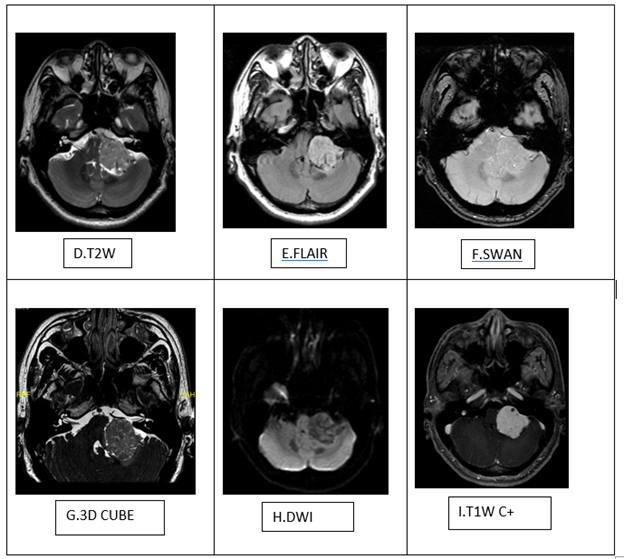

Bệnh nhân nam 41 tuổi tiền sử khỏe mạnh, đến khám với triệu chứng đau đầu vùng chẩm và thỉnh thoảng bị giảm thị lực khoảng vài tuần trước khi vào viện. Hình ảnh cộng hưởng từ sọ não trước và sau tiêm đối Gadolinium tĩnh mạch cho thấy khối giới hạn rõ, bờ khá đều, kích thước # 35x32x29mm, giảm nhẹ tín hiệu không đồng nhất trên T1, tăng nhẹ trên T2, FLAIR, SWAN, 3D CUBE, không hạn chế khuếch tán, ngấm thuốc đối quang từ mạnh không đồng nhất sau tiêm. choán chỗ ở góc cầu tiểu não trái (Hình 1.A-I). Khối chèn đẩy hành não và não thất IV sang phải (Hình 1A, B), đẩy dây thần kinh tiền đình (dây VIII) trái lên trên ra trước (1.A,D,G) và đẩy bán cầu tiểu não trái lên trên, gây phù cuống tiểu não trên trái (1.C,E). Không thấy giãn hệ thống não thất hay não úng thủy. Không có khối bất thường khác. Bệnh nhân được chẩn đoán u góc cầu tiểu não trái, khả năng u bao dây thần kinh (Schwannoma) VIII.

Hình 1. Hình ảnh khối giới hạn rõ, bờ khá đều, giảm nhẹ tín hiệu không đồng nhất trên T1 (A), tăng nhẹ trên T2(D), FLAIR(E), SWAN (F), 3D CUBE (G), không hạn chế khuếch tán(H), ngấm thuốc đối quang từ mạnh không đồng nhất sau tiêm(I) ở góc cầu tiểu não trái. Khối chèn đẩy hành não và não thất IV sang phải (Hình 1A, B), đẩy dây thần kinh tiền đình (dây VIII) trái lên trên ra trước (1.A, D, G) và đẩy bán cầu tiểu não trái lên trên, gây phù cuống tiểu não trên trái (1.C,E)